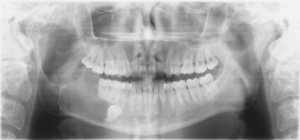

Der vorliegende Fallbericht beschreibt die Behandlung eines jungen Soldaten mit einer Kronenfraktur an einem wurzelkanalbehandelten Zahn. Der Patient stellte sich vor, weil er einen ungewöhnlichen Geschmack im Mund verspürt habe. Eine eingehende klinische und radiologische Untersuchung ergab eine leichte Lockerung des Zahnes 11 sowie den Verdacht einer Querfraktur (Abb. 1). Der Patient trug einen Retainer im Ober- und Unterkiefer, das die Herangehensweise zusätzlich beeinflusste.

Ein junger Soldat stellte sich während eines Lehrgangs in der Zahnarztgruppe mit Beschwerden am Zahn 11 vor. Er nahm seit einiger Zeit einen merkwürdigen Geschmack im Mund wahr und habe das Gefühl, dass sich der Oberkiefer-Retainer gelockert habe. Anamnestisch berichtete der Patient, dass die Zähne 12 und 11 nach einem Frontzahntrauma in der Kindheit wurzelkanalbehandelt wurden. Eine kieferorthopädische Therapie war abgeschlossen, und der Patient befand sich in der Retentionsphase mit Drahtretainer im Ober- und Unterkiefer (Abb. 1). Er berichtete von keinen besonderen Vorkommnissen, die auf ein Trauma hinwiesen. Der intraorale Befund zeigte eine Lockerung des Zahnes 11 (Lockerungsgrad I). Bei Bewegung des Zahnes 11 konnte vestibulär im Sulkus ein Bruchspalt erkannt werden. Zudem war Zahn 41 nach labial gekippt, was offenkundig zu einer Überbelastung von Zahn 11 (substanzgeschwächt durch die Wurzelkanalbehandlung) und dadurch zur Fraktur führte.

Ein angefertigter Zahnfilm zeigte eine Kontinuitätsunterbrechung im Bereich des Zahnhalses, was auf eine Frakturlinie hindeutete (Abb. 1b). Apikal waren die Zähne unauffällig, von einem apikalen Geschehen bei technisch suffizienter und bis zum röntgenologischen Apex reichenden Wurzelfüllung war nicht auszugehen. Die Verdachtsdiagnose lautete: Querfraktur des Zahnes 11, etwa 1 mm subgingival. Verschiedene Behandlungskonzepte wurden diskutiert, einschließlich einer direkten Konsultation mit einem Oralchirurgen, um die Möglichkeit einer (Sofort)Implantation zu erörtern.